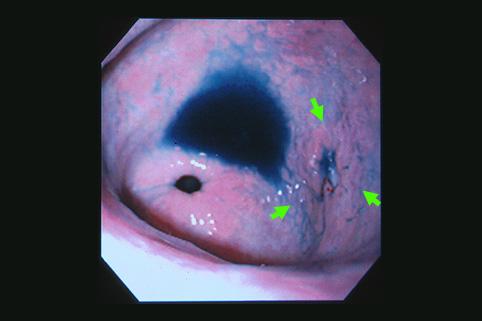

clasificación del pacienteTumor Epitelial Maligno/Adenocarcinoma

parte(separada por órganos)estómago(región)/antro

método de exámenEndoscopia

clasificación ectoscópica de tumoresTipo 0(tipo superficial)/Tipo IIc(IIc)

diámetro mayor del tumor1 - 9

grado de penetraciónm